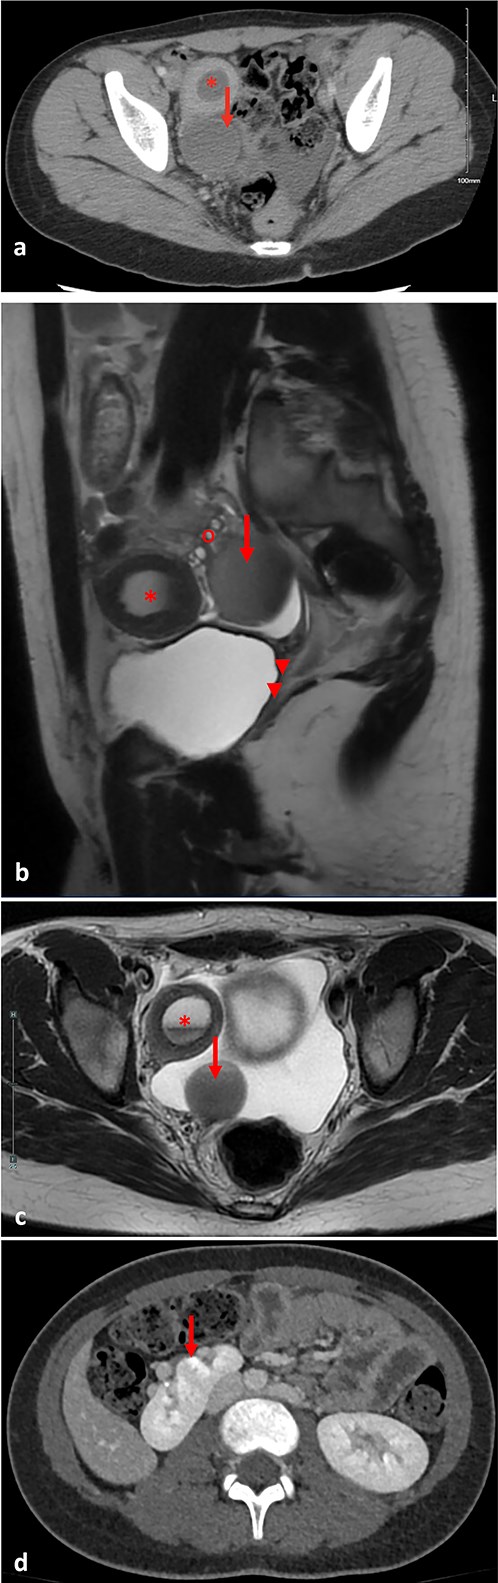

An abdominal ultrasound was done to rule out appendicitis and showed free fluid in the right lower quadrant. A follow-up pelvic ultrasound showed a complex right adnexal cystic structure. A computed tomography abdomen/pelvis (CT AP) was performed and showed an abnormally positioned uterus in the right hemipelvis with hematometra, no identifiable cervix, a right adnexal cystic structure measuring 3.7 cm, free fluid in the pelvis, and a supernumerary right kidney fused to the native right kidney. This constellation was suggestive of a Mullerian duct anomaly. Pelvic magnetic resonance imaging (MRI) demonstrated a right unicornuate uterus with hematometra with an absent left horn, a right dilated hematosalpinx measuring 3.8 cm, a left ovary displaced to the anterior left lower quadrant, cervical aplasia, and vaginal atresia consistent with a Mullerian duct anomaly (U5a C4 V4) (Fig. 1).

(a) Pre-operative axial computed tomography imaging, demonstrating a right uterine horn with hematometra (*) and a right adnexal cystic structure representing hematosalpinx (arrow). (b) Pre-operative pelvic parasagittal T2 weighted MRI, demonstrating a right uterine horn with hematometra (*), a right adnexal cystic structure representing hematosalpinx (arrow), normal right ovary (o), cervical aplasia, and vaginal atresia (arrowheads). (c) Pre-operative pelvic axial T2 weighted MRI, demonstrating a right uterine horn with hematometra (*), and a right adnexal cystic structure representing hematosalpinx (arrow). (d) Pre-operative abdominal axial T2 weighted MRI, demonstrating a right supernumerary kidney (arrow).